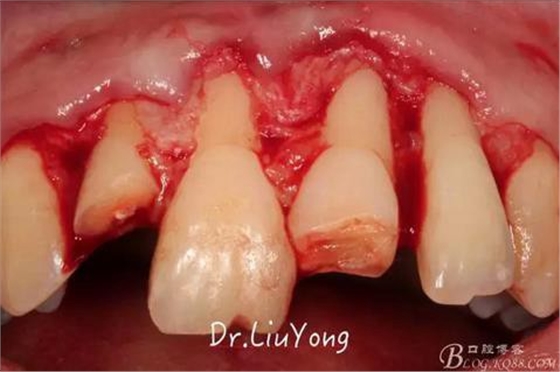

術(shù)中,可見明顯的唇側(cè)骨開裂,如上圖